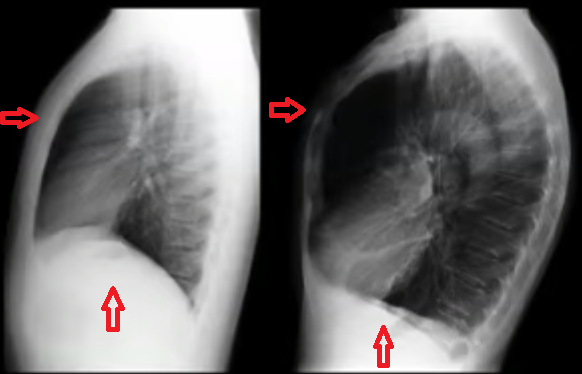

O que é isso? Derrame cisural / cissuras pulmonares

Quais são os achados radiológicos do derrame pleural? O que pode causar a doença? -Presença de muito líquido no espaço pleural -Obliteração do seio costofrênico (preenchimento do espaço entre as costelas e o diafragma) -Imagem em menisco -Elevação da cúpula diafragmática -Lawrell pode deslocar o líquido; Tuberculose e neoplasias (Doença pleural), insuficiência cardíaca e congestiva (Doença sistêmica)

Quais são os sinais radiológicos de derrame pleural? Opacificação do espaço pleural, sinal do menisco, deslocamento do diafragma e fissuras pleurais.